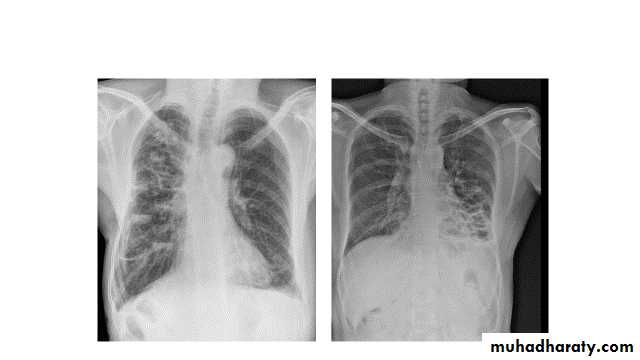

Post primary TB radiographic appearance

Post-primary pulmonary tuberculosis, also known as reactivation tuberculosis or secondary tuberculosis occurs years later, frequently in the setting of a decreased immune status. In the majority of cases, post-primary TB within the lungs develops in either :

* posterior segments of the upper lobes

*superior segments of the lower lobes

Typical appearance of post-primary TB

1.patchy consolidation or poorly defined linear and nodular opacities in both apices , upper zone in one lung , & lower zone in other lung ( ulternating lesion ) .2. Post-primary infections are far more likely to cavitate with multiple abscess formation & air fluid level more develop in the posterior segments of the upper lobes.

3. Tuberculomas seen in post-primary TB and appear as a well defined rounded mass typically located in the upper lobes .

4. Miliary tuberculosis is uncommon but carries a poor prognosis. It represents haematogenous dissemination of an uncontrolled tuberculous infection. It is seen both in primary and post-primary tuberculosis. Although implants are seen throughout the body, the lungs are usually the easiest location to the image. Miliary deposits appear as 1-3 mm diameter nodules . are uniform in size and uniformly distributed